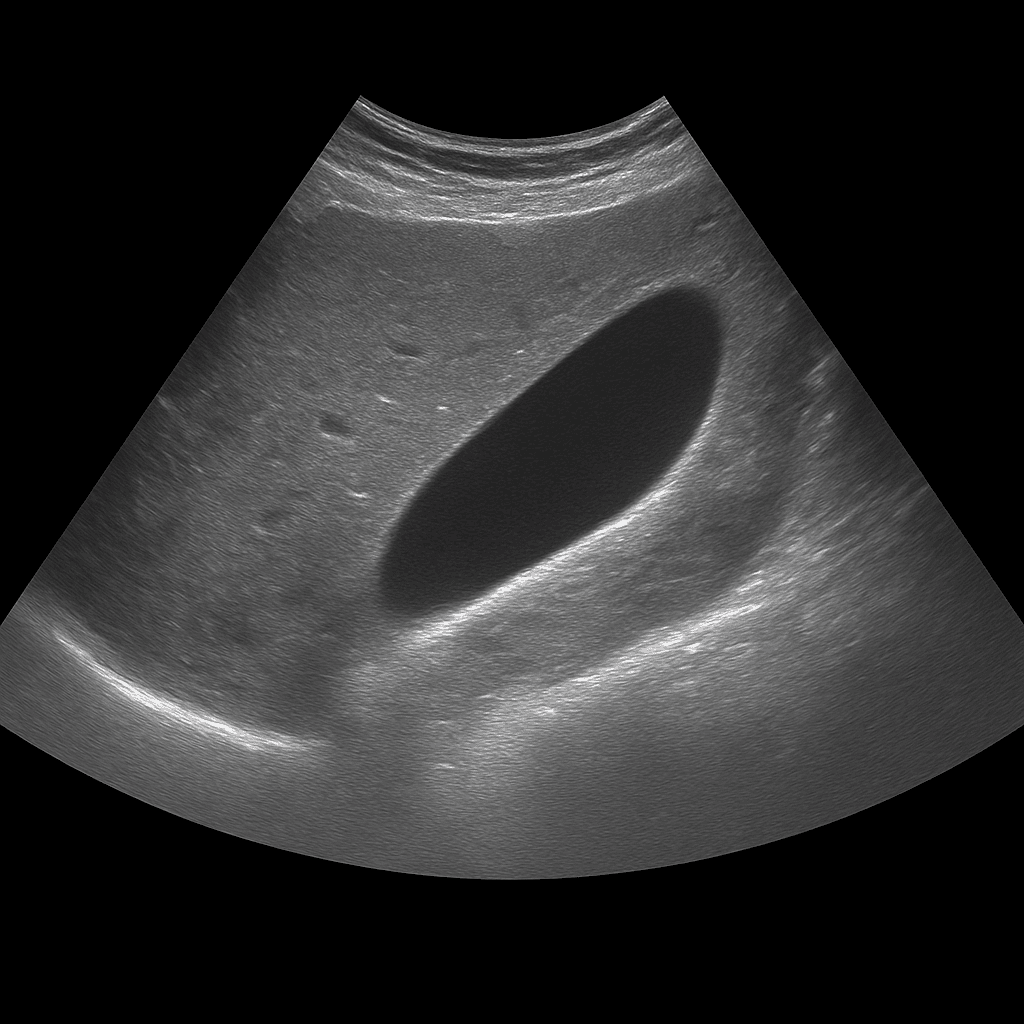

Ett ultraljud av gallblåsan används för att undersöka gallblåsans vägg, innehåll och funktion. Undersökningen utförs av specialistläkare inom radiologi och ger detaljerade bilder i realtid som visar om gallblåsan innehåller stenar, vätska eller tecken på inflammation. Ultraljud gallblåsa används som förstahandsmetod vid misstanke om gallstenssjukdom eller inflammation i gallblåsan (kolecystit).

Ultraljud gallblåsa rekommenderas vid smärta under höger revbensbåge, illamående, uppblåsthet eller återkommande obehag efter fettrik mat. Undersökningen kan visa om gallblåsan innehåller stenar, slam (gallgrus) eller förtjockad vägg som tyder på inflammation. Den används också för att följa upp tidigare gallstensbesvär eller efter operation där delar av gallvägssystemet finns kvar.

Till skillnad från ultraljud av gallvägar, som fokuserar på gallgångarna och deras förbindelse med levern, är ultraljud gallblåsa inriktad på själva gallblåsans vägg, innehåll och funktion. Metoden används för att upptäcka akuta eller kroniska förändringar i organet, medan MR eller DT används när man behöver bedöma gallgångar och omgivande organ mer i detalj.

Undersökningen utförs medan du ligger på rygg eller lätt på vänster sida. En gel appliceras på huden och läkaren för ultraljudsproben över området under höger revbensbåge. Undersökningen tar vanligtvis 10–20 minuter. För bästa bildkvalitet behöver du vara fastande i minst 4–6 timmar innan, eftersom en tom gallblåsa är svår att bedöma.